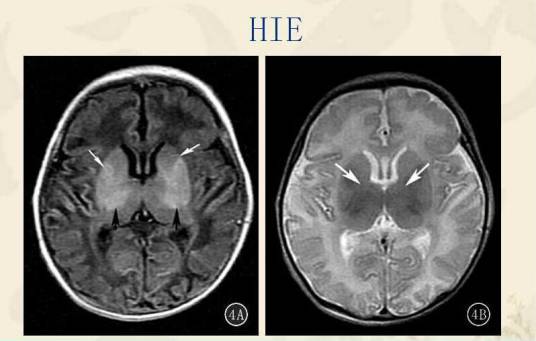

胆红素脑病,过去称核黄症。是指高非结合胆红素血症时,游离胆红素通过血脑屏障,沉积于基底神经核、丘脑、丘脑下核、顶核、脑室核、尾状核、以及小脑、延脑、大脑皮质及脊髓等部位,抑制脑组织对氧的利用,导致脑损伤。